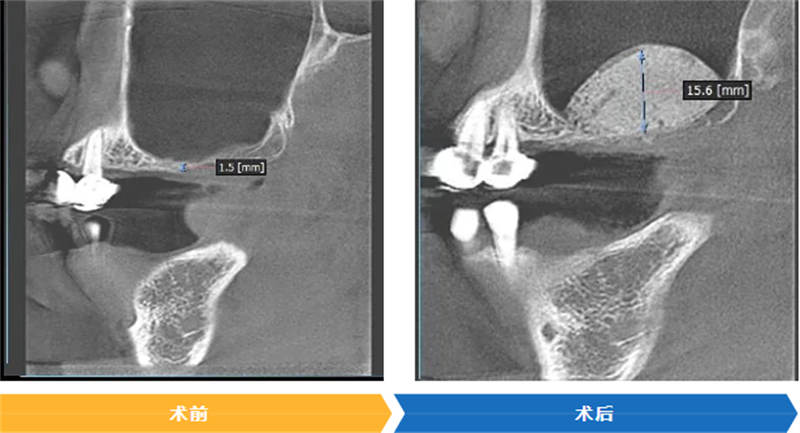

CBCT檢查顯示,藍(lán)女士右上后牙區(qū)牙槽骨垂直高度不足2mm,臨床診斷為牙列缺失伴隨垂直向頜骨缺損,不符合常規(guī)種植條件。為了幫助藍(lán)女士實(shí)現(xiàn)重新舒適進(jìn)食、提升生活品質(zhì)的目標(biāo),口腔科啟動(dòng)多學(xué)科聯(lián)合會(huì)診,最終確定采用Sticky Bone技術(shù)實(shí)施引導(dǎo)骨再生手術(shù),為后續(xù)的種植修復(fù)創(chuàng)造基礎(chǔ)。

隨后,醫(yī)師精準(zhǔn)將這種“生物粘合劑”植入右側(cè)上頜竇底的骨缺損區(qū)域。術(shù)后復(fù)查顯示,藍(lán)女士該區(qū)域牙槽骨量顯著增加,為種植體植入預(yù)留了充足條件。“沒(méi)想到這么順利就能解決問(wèn)題,感覺(jué)像獲得了新生!”藍(lán)女士難掩激動(dòng)。